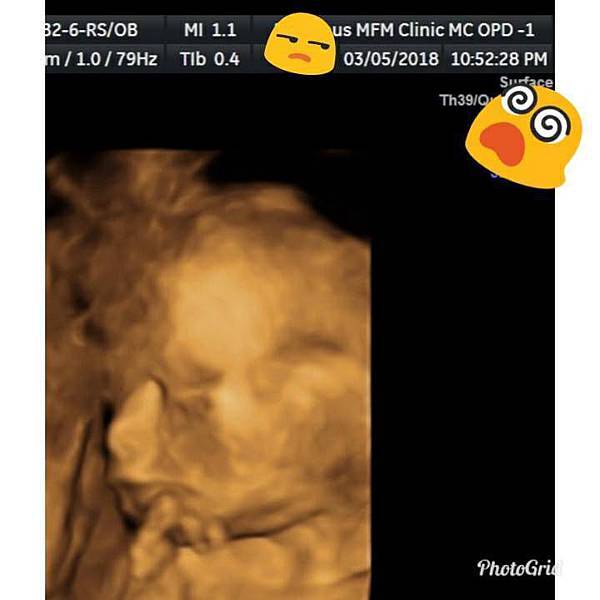

阿木自費的高貴高層次超音波檢查就是想把鵝仔給看個清楚,一開始趴著不說,手還給我把臉給全遮住,肚子被兔到不行,動也不給我動一下。